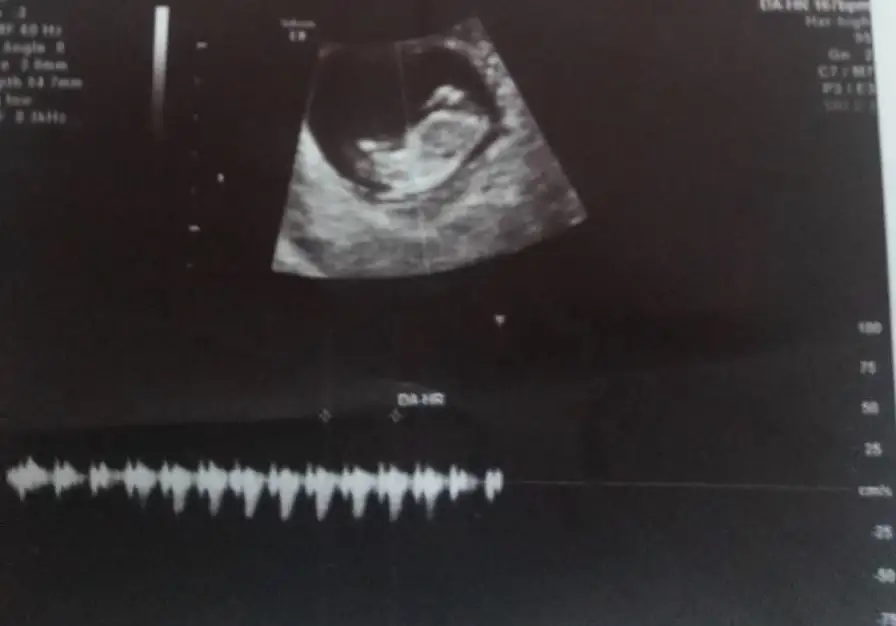

ikili tarama sonrası. Sizce cinsiyeti nedirr? Doktor bi tahmin de bulundu ama daha erken tabi ☺️☺️

Usg net değil emin olmadım başka usg de paylaşın 12 13 hafta olursa şimdilik sanki erkek gibi gibi 😬

Kız sanki burada nubu ne dik nede paralel karşıya bakıyor 😊 önceki usgde erkek gibiydi 😄

😂 Tahminim kız ama daha tam oluşmamış üç haftası var oluşması icin dedi doktor.tabi ki hayırlısı olsun saglıklı hayırlı evlat olsun ama gönlümden gecen kız olması bakalım bekleyip görücez.tesekkürler tahmininiz için ❤️